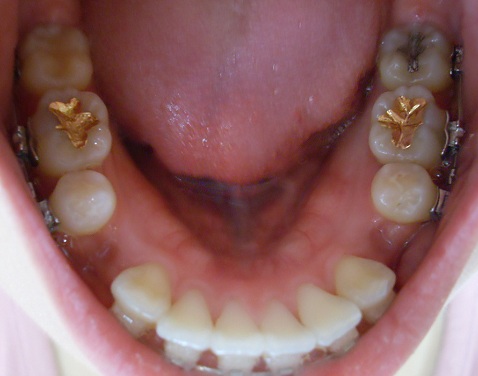

하악사진

고무줄을 다른 걸루 바꿨는데 처음 고무줄로 당기는 것보다 훨!!!씬 안아프네요